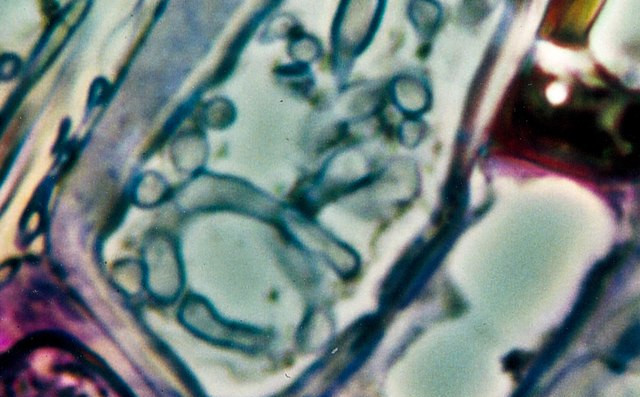

Raziskovalke in raziskovalci so dodatno preverjali prisotnost gliv v tkivnih preparatih raka trebušne slinavke, dojk, pljuč in jajčnikov ter kožnega raka s štirimi različnimi metodami barvanja. Glive, ki so jih videli na tkivnih preparatih, so večinoma rasle v rakavih ali imunskih celicah.

Vir slike: https://commons.wikimedia.org/